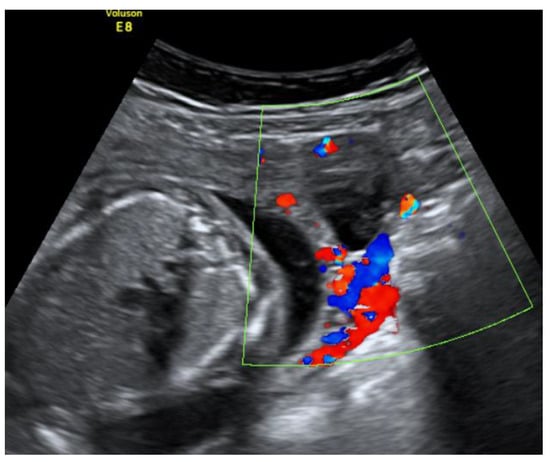

An urgent Magnetic Resonance Imaging (MRI) was performed. A 36 × 20 × 36 mm size cystic mass with T2-hyperintense wall in the left cornual region was observed. An MRI scan also showed one more fetus inside the uterine cavity with placenta located on the left lateral wall. Figure 2 The diagnosis of a heterotopic angular pregnancy in the left cornu of the uterus was established. The patient was hospitalized for further observation.

Figure 2. MRI scan of the uterus on the 13w + 3d.